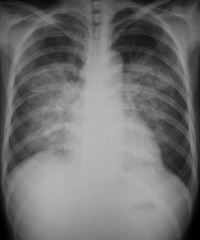

肺水肿间质期的X线表现主要为肺血管纹理模糊,增多,肺门阴影不清,肺透光度降低,肺小叶间隔增宽。两下肺肋膈角区可见与胸膜垂直横向走行的KerleyB线,偶见上肺呈弧形斜向肺门较KerleyB线长的KerleyA线。肺泡水肿主要表现为腺泡状致密阴影,呈不规则相互融合的模糊阴影,弥漫分布或局限于一侧或一叶,或从肺门两侧向外扩展逐渐变淡成典型的蝴蝶状阴影。有时可伴少量胸腔积液。但肺含量增加30%以上才可出现上述表现。CT和核磁共振成像术可定量甚至区分肺充血和肺间质水肿,但费用昂贵。

- 分布和形态呈多样性,可呈中央型、弥漫型和局限型。中央型表现为两肺中内带对称分布的大片状阴影,肺门区密度较高,形如蝶翼称为蝶翼征。局限型可见于一侧或一叶,多见于右侧。除片状阴影外,还可呈一个或数个较大的圆形阴影,轮廓清楚酷似肿瘤。